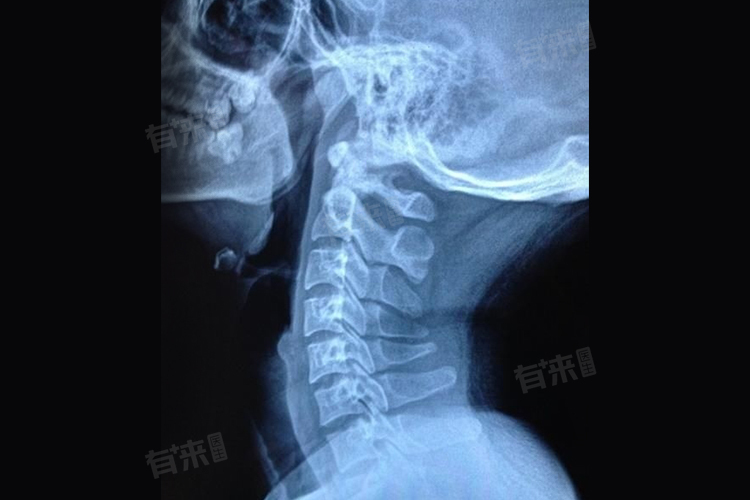

颈椎韧带钙化是一种较为常见的颈椎病变情况,主要是指颈椎部位的韧带组织中出现了钙质沉积,使得韧带变硬、失去弹性,通常难以自愈。

- 一旦颈椎韧带发生钙化,其病理改变往往是不可逆的。钙化的韧带组织已经失去了正常的弹性和柔韧性,很难自行恢复到原来的状态。而且,钙化的韧带可能会对周围的神经、血管等组织造成压迫,引起一系列的症状,如颈部疼痛、僵硬、活动受限、上肢麻木等。